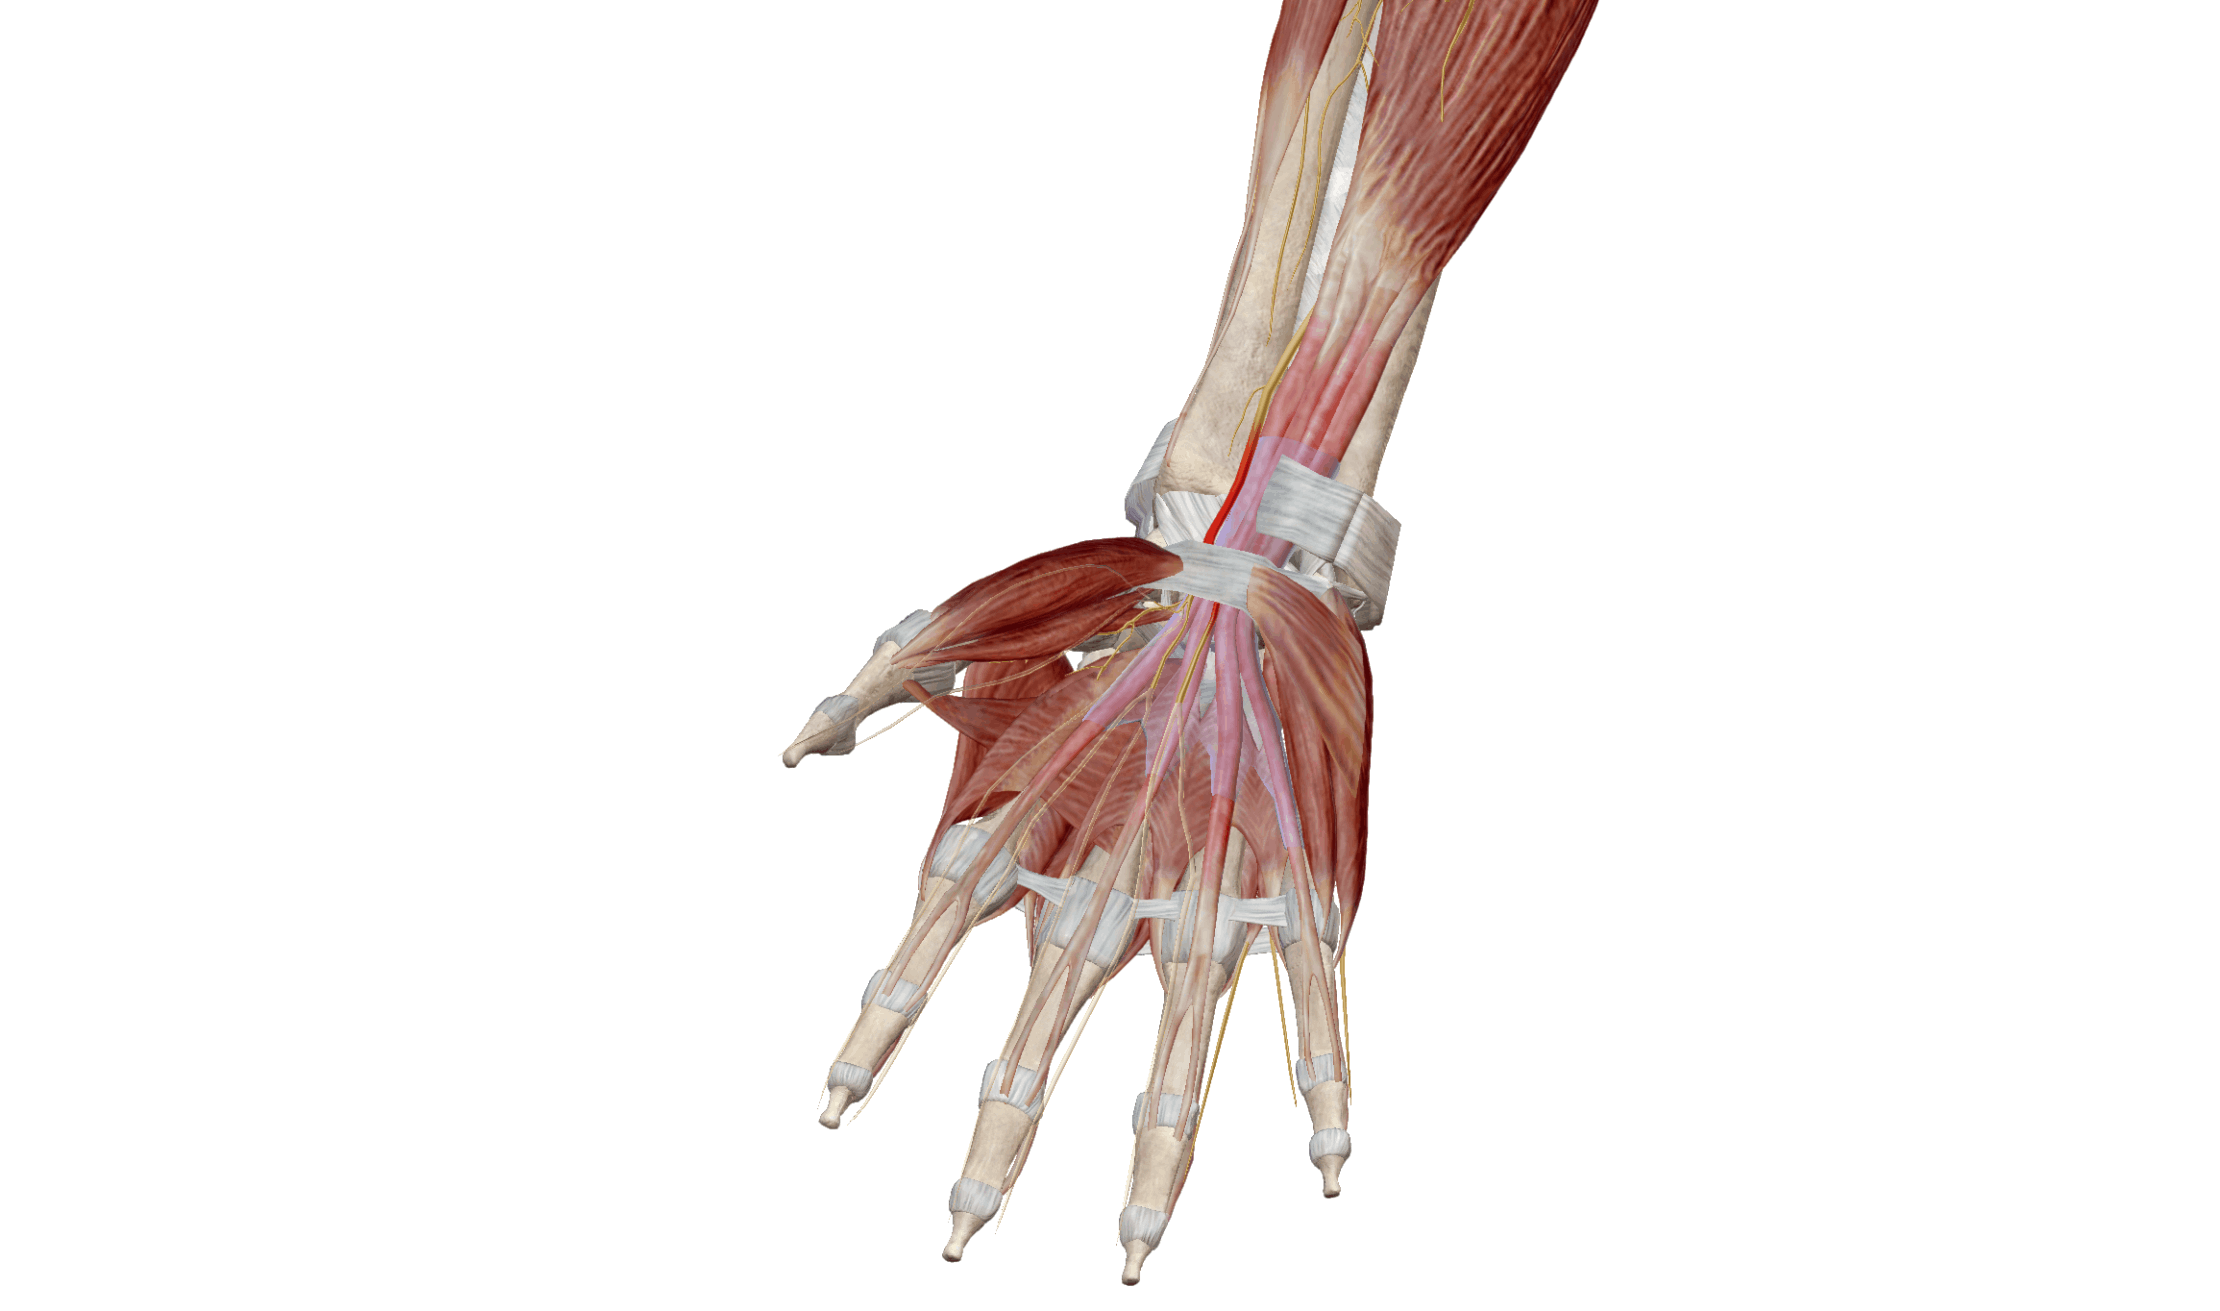

Le syndrome du canal carpien est une affection courante qui provoque des douleurs, des engourdissements et des picotements dans la main et le poignet. Ces symptômes sont causés par la compression du nerf médian, un nerf important qui traverse le canal carpien, un passage étroit au niveau du poignet.

Gonflement des tissus: Une inflammation ou un gonflement des tendons ou des ligaments dans le canal carpien peut exercer une pression sur le nerf.

Engourdissements et picotements: Ces sensations sont souvent ressenties dans le pouce, l'index, le majeur et la moitié de l'annulaire.